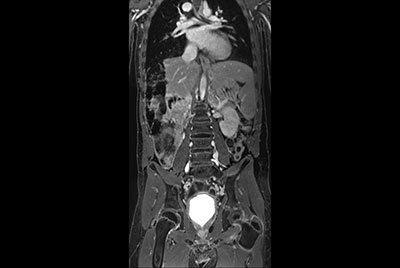

Abdomen large FOV imaging